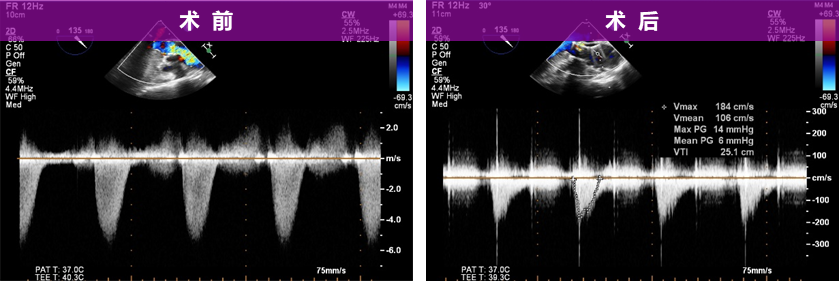

跨瓣压差:

超声影像:

20mm球囊后扩后支架腰部形态接近理想膨胀状态,瓣周漏微量。

植入后血流动力学有效改善,术后Vmean 1.06m/s Pgmean 6mmHg。